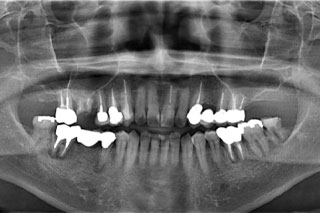

レントゲン写真

レントゲンを撮影すると右下の奥歯の歯根が割れてしまっており、保存不可能な状態でした。

| 治療内容 | 噛むと痛い、歯茎から血が出るとのことで来院されました。 レントゲンを撮ると右下の歯が歯根破折しており保存不可能なため抜歯をしました。 ブリッジや入れ歯を入れると残っている歯に負担がかかるためインプラント治療をしていくことになりました。 何を噛んでも痛くないと満足していただきました。 |